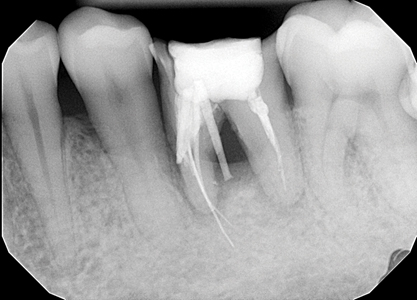

Viewpoint FIGURE #1 alternate text for this image

Many of our patients are attracted to the allure of cheaper dental treatment abroad. Tooth #36 in the accompanying radiograph (Fig. 1) and photo (Fig. 2) is an example of such a case. Unfortunately in this case, almost every possible iatrogenic endodontic mishap was encountered. This treatment is substandard and if done in Canada the … Read more